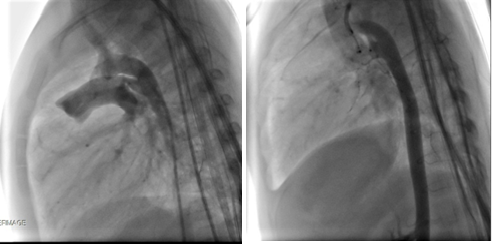

- TAVR as treatment of choice in severe aortic regurgitation with multivalve pathology and chronic kidney disease patientHeart valvular diseases